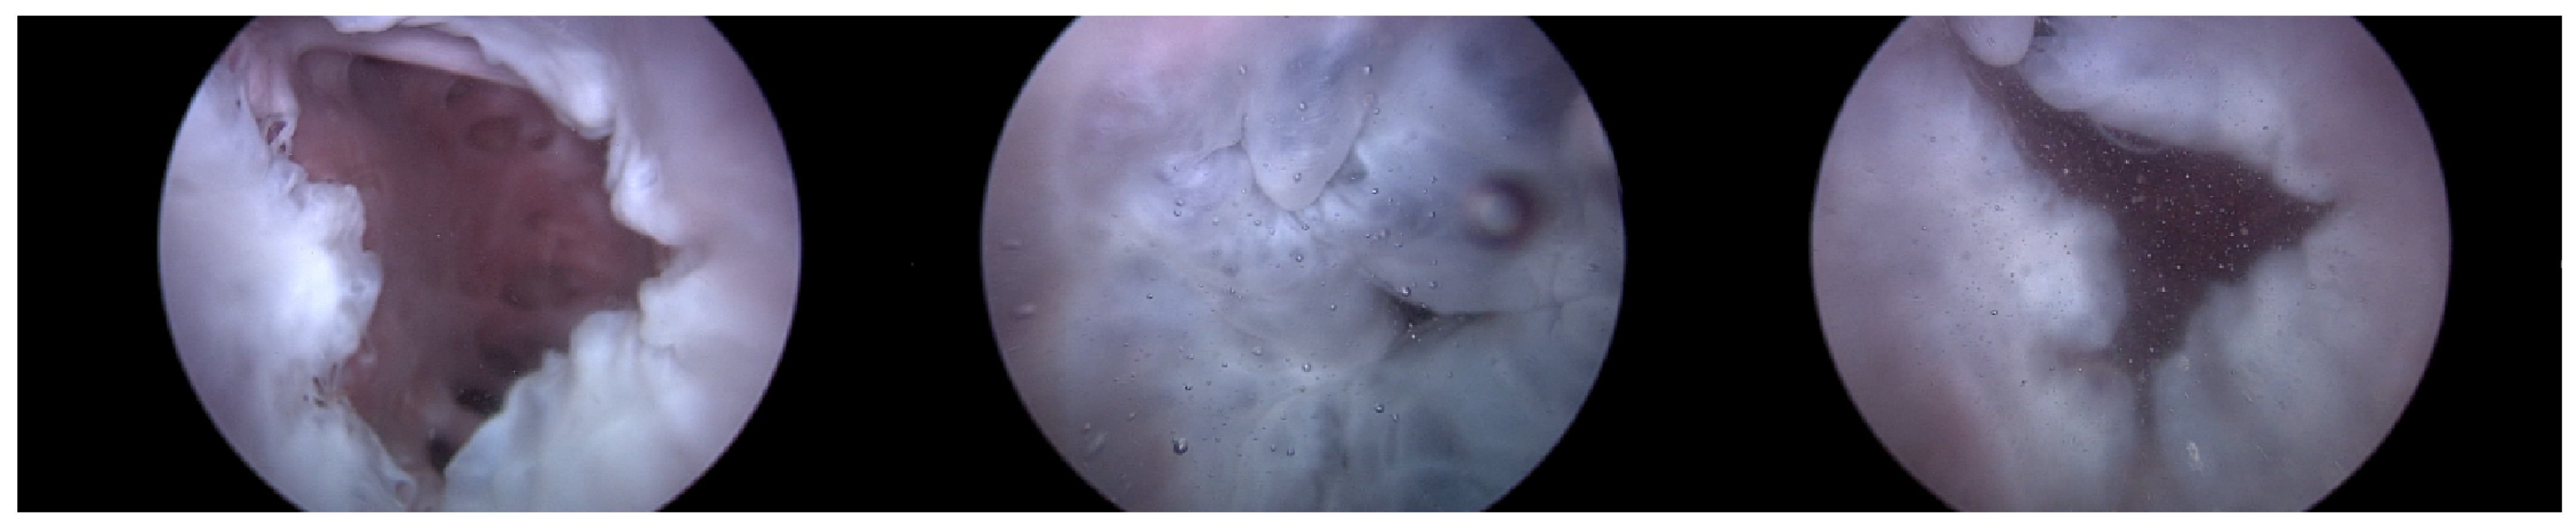

Heart 2 with Pivot-TR, as in Figure 15, was subjected to experimentation following the confirmation of the reproducibility of results of Heart 1 and Heart 2 without the Pivot-TR device; the difference in peak pressure values was revealed in the spectrum analysis between the normal and abnormal phases in Table 1. The ‘Dominant Pressure’ data shown in Table 1 were generated based on settings established by the simulator, while the ‘Peak Pressure’ values are simulated results induced by simulator and TRG settings. The main objective was to assess the extent to which Pivot-TR, when installed on the TV of a porcine heart, could alleviate the manifestation of TR. Unlike the previously observed conditions in Heart 1 and Heart 2 experiments where TR was evident, the presence of Pivot-TR significantly attenuated these conditions. As depicted in Figure 16 and Figure 17, the functionality of the TV consistently remained in the normal phase throughout.

Upon comparing the two scenarios of Heart 2, especially within the 50–100 bpm range, the amplitude was observed to be merely 10% in the second scenario (Figure 17) compared to that in the first (Figure 14). This suggests that Pivot-TR operates similarly to a low-pass filter, attenuating the blood pressure oscillations occurring in the RA and RV.

Nonetheless, this study marked distinct progress. Transitioning from indirect imaging techniques to optical endoscopic methods has significantly improved the resolution and clarity of images. The shift from previously low-resolution images, which provided limited insights into heart and Pivot-TR dynamics, to high-resolution endoscopic imaging has enriched our understanding.

Figure 15. Endoscopic image of Heart 2 with Pivot-TR (valve open, normal valve closed).